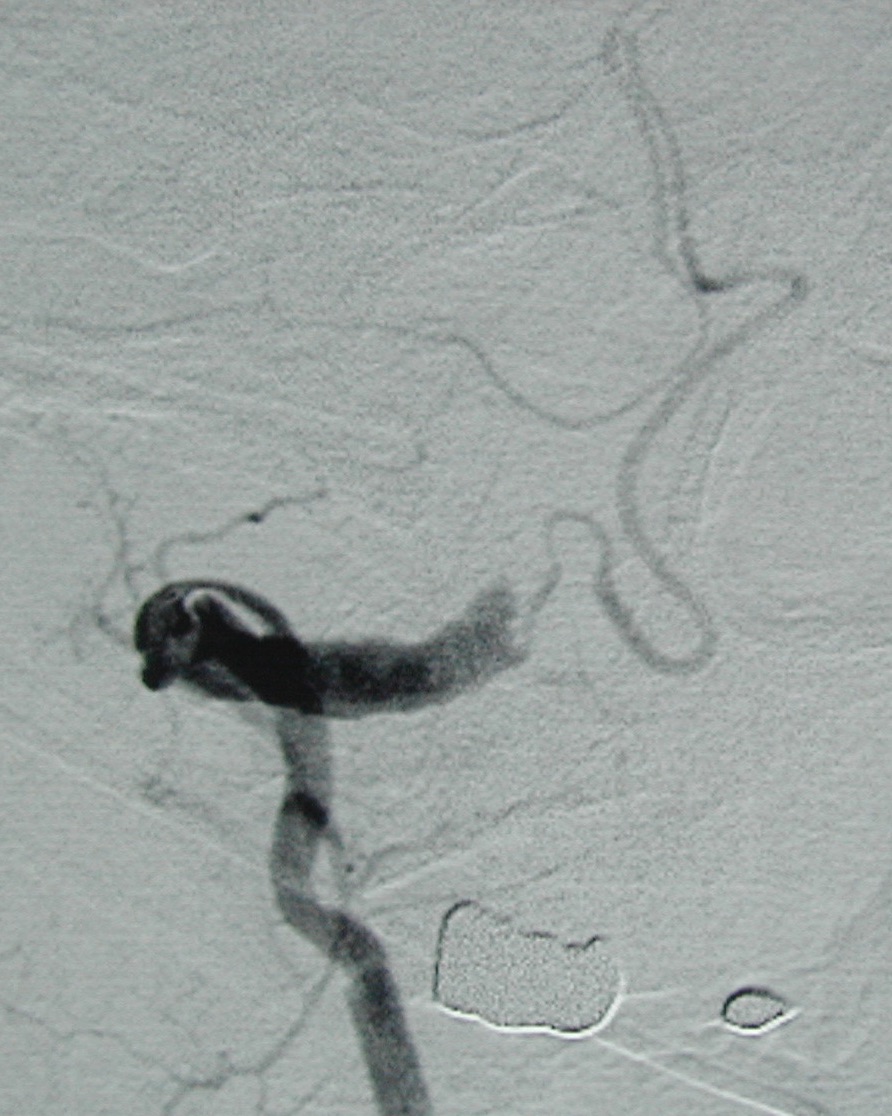

49歳、男性

主訴:意識消失

現病歴:平成12年11月10日頃より頭痛あった。同年11月13日早朝にも頭痛があったが酒のためかと思っていた。午前9時30分頃、喫茶店で突然気分不良となり意識消失した。救急車が到着した時には意識回復していた。9時44分当院到着。3回嘔吐した。

治療:血管内治療(親動脈および瘤内コイル塞栓術)

<入院時の頭部CT;くも膜下出血を認める>